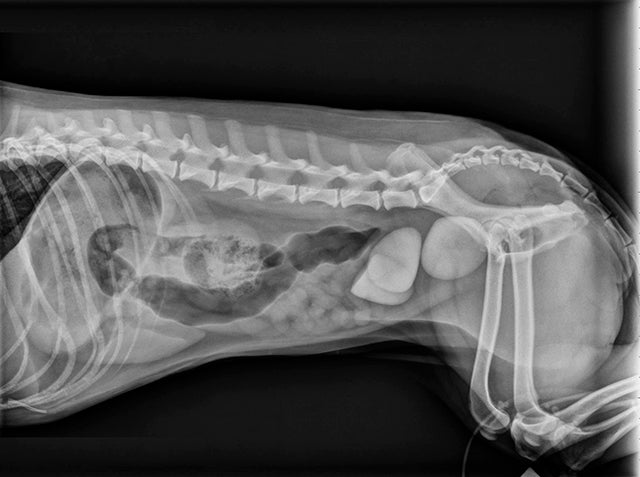

Is that a finger in that x-ray?

In this VETgirl veterinary technician webinar, Amy Cardwell, CVT, VTS will review how to perform a variety of non-manual restraint techniques for imaging small animal veterinary patients. Tune in to brush up on all you need to know about x-ray technique!